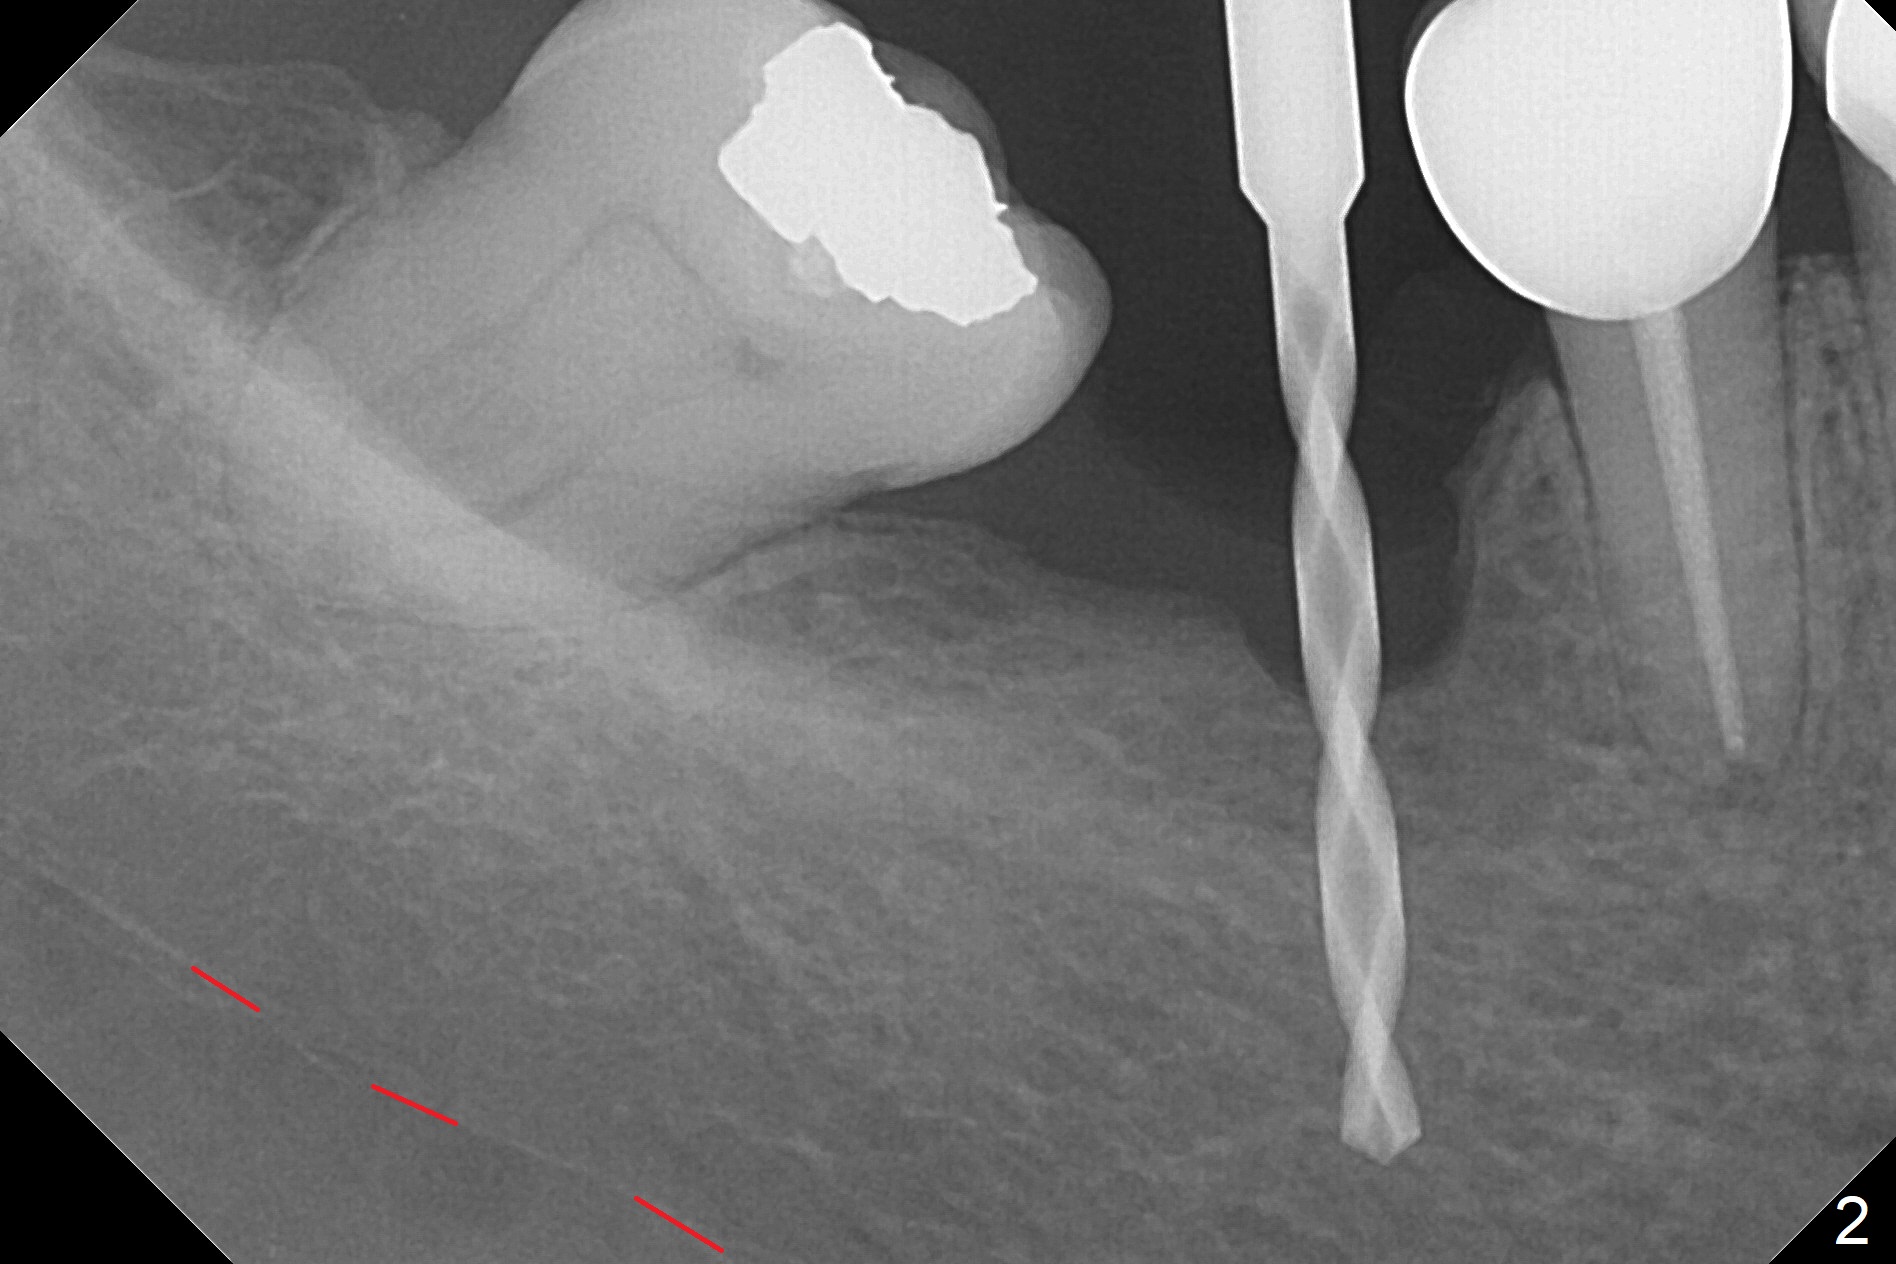

Incision reveals a narrow ridge and a narrow mesiodistal space at #30 (Fig.1). It seems that a 1-piece implant is indicated. Due to limited mouth opening, a 1.2 mm drill is unstable in place after use for 10 mm; instead a 1.5 mm drill is able to be inserted for 8 mm (Fig.2). A 3x10(2) mm 1-piece dummy implant is placed with 40 Ncm at an apparently acceptable level (Fig.3 >). Clinically a few threads are exposed buccally. When a definitive implant with the same dimension is inserted with 45 Ncm, it looks seated too deep (Fig.4,5). The latter is noted after suturing. The implant is backed up for a few turns so that the length of the abutment appears a little more reasonable. Introspectively, a 4 mm cuff should have been used after ridge reduction. Although there is no bone loss 4 months postop (Fig.6), the abutment margin (Fig.7 arrow) is subgingival (red dashed line: gingival margin). Diode laser is used for gingivectomy prior to impression. The bone density around the implant increases 11 months post cementation (Fig.8 *), probably related to recurrent #18 infection. The patient uses floss after meal.